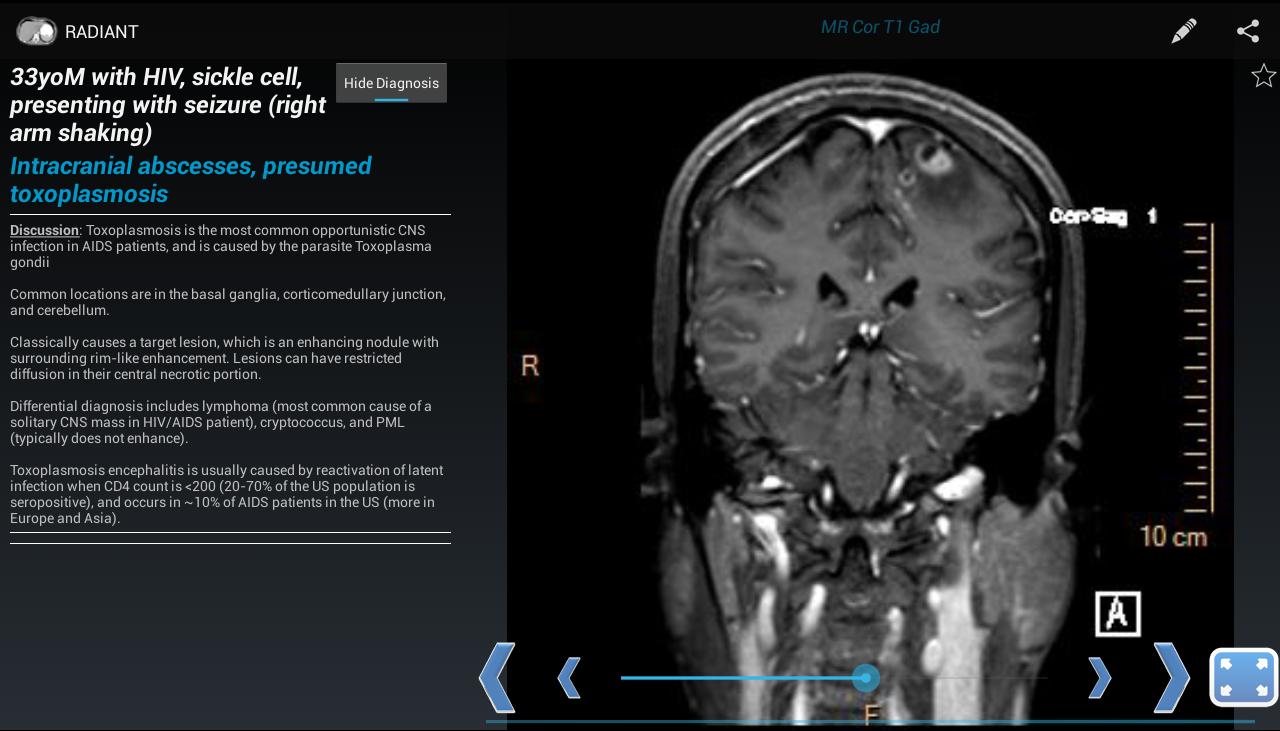

放射を使用すると、X線、超音波、CT、MRI、またはその他のイメージングモダリティを示すケースを作成できます。これは、実際の高品質の診断医療画像を使用して、胸部X線、正常な解剖学、および一般的な疾患プロセスを学ぶのに最適な方法です。